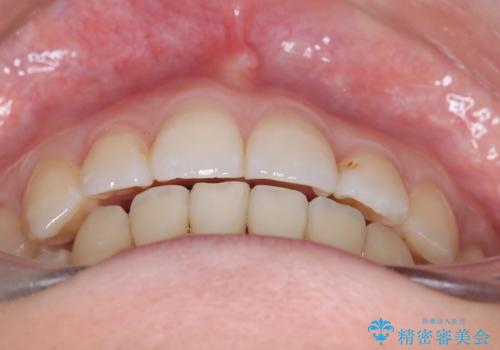

- 主訴:口元を下げて前突感を無くしたい、下の歯の凹凸も無くしたい

右側第二小臼歯、左側第一小臼歯、下顎両側第一小臼歯を抜歯しワイヤ-矯正を行いました。

骨格的顎の変位を認めたため、顔貌に対しピッタリ上下の歯の正中を合わせることは難しいと説明し、上下左右計4本小臼歯を抜歯しワイヤー矯正治療を行いました。